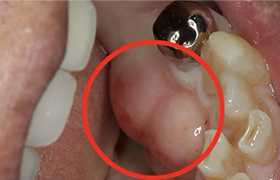

歯牙移植(歯の移植)

むし歯や歯周病で歯を失った後に、通常必要のない親知らずを、なくなった箇所に移植することによって健康な歯並びを回復する事ができます。

※移植には適合のための条件があります。

Before

After